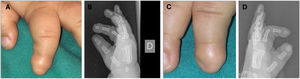

Clinically, we can see loss of the normal curvature of the nail plate. The central part is depressed, and the lateral edges are everted, resulting in a concave transverse axis of the nail3,5,8 (Fig. 1B).

Congenital hypertrophy of the nail folds of the first toeThis condition appears at birth or within the first few days of life and usually resolves spontaneously within the first year. It is due to the asynchrony between the growth of the nail plate and periungual tissues.3,4,6,8 It is characterized by hypertrophy of the periungual soft tissues—preferably the lateral folds although the distal folds are involved too—of the first toe.3,4,6,8 It can occasionally partially or completely cover the nail plate (Fig. 1C). Possible complications include paronychia, misalignment of the nail plate, koilonychia, or onychocryptosis.4,6 No therapy is necessary, only massaging the hypertrophied fold. Occasionally, treatment with topical corticosteroids or antibiotics is prescribed to control associated secondary inflammation or infection, sparing surgical management for cases that do not resolve within the first year of life.3,4,8